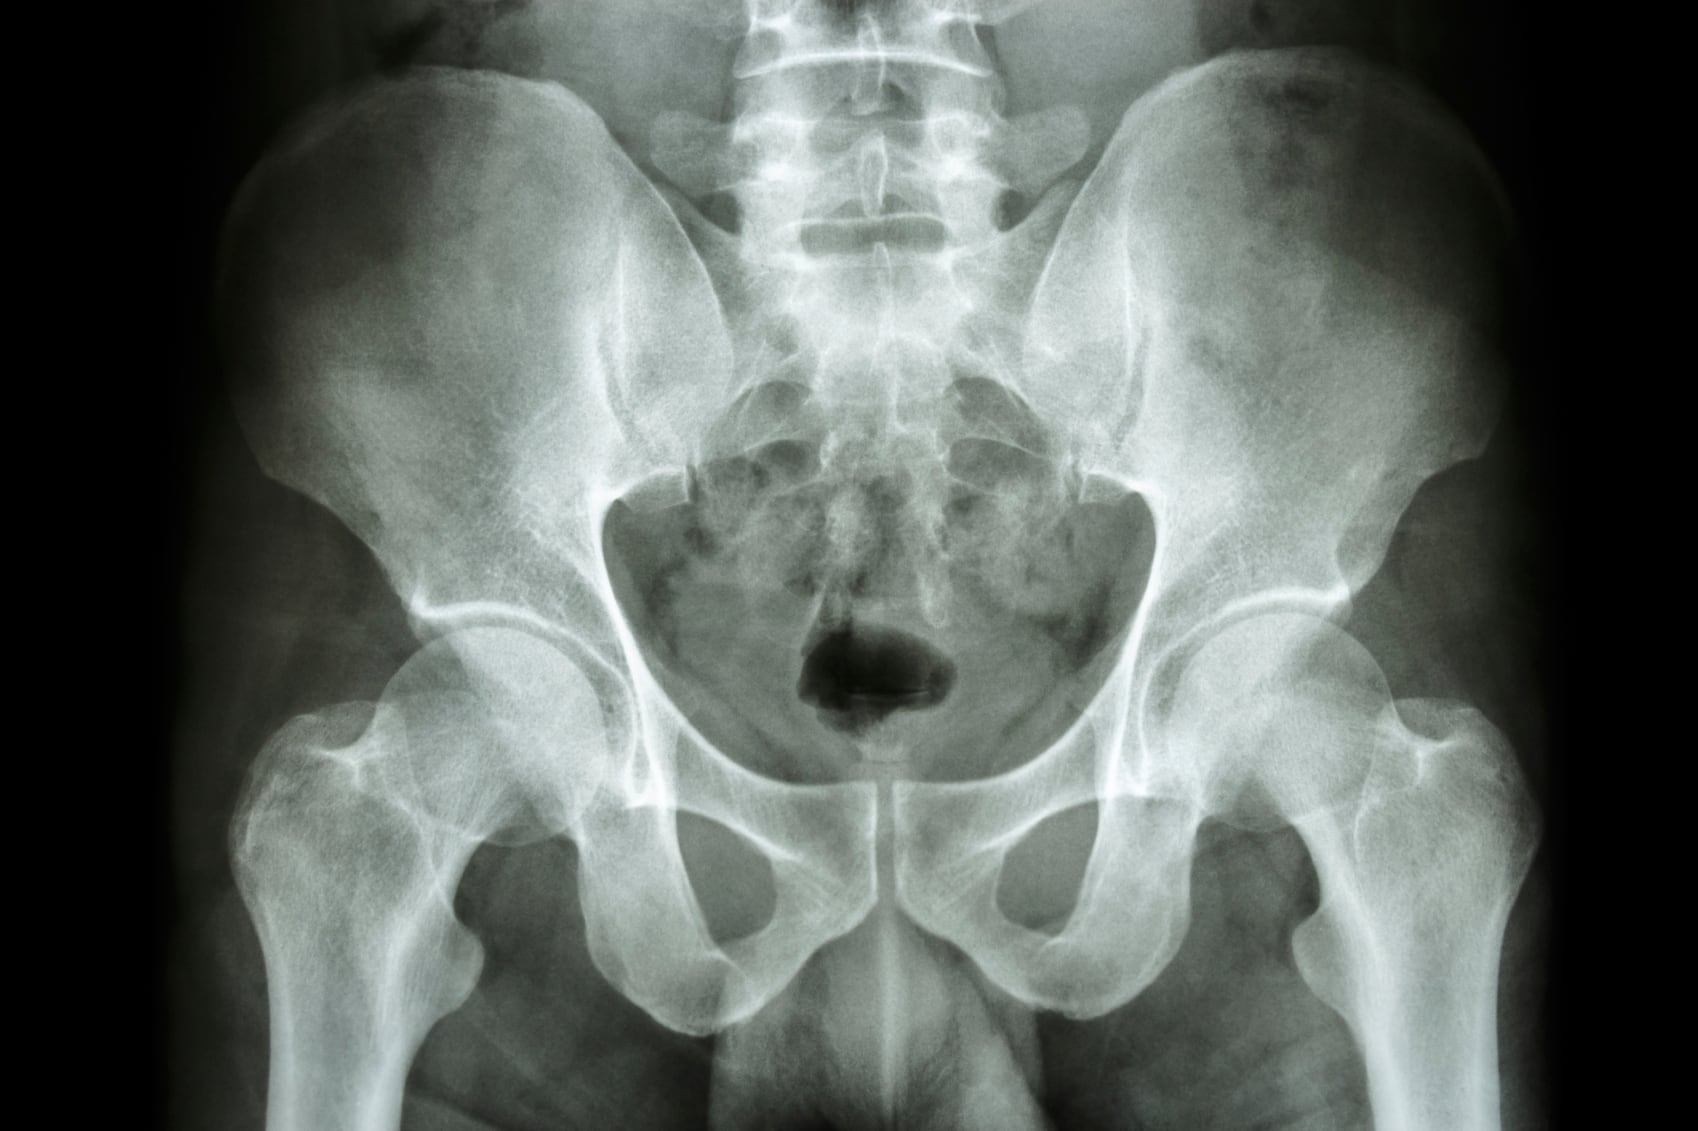

Osteoporosis has been described as a silent killer, and recent data from the National Osteoporosis Foundation showed that approximately 9 million American adults currently have osteoporosis and another 48 million have low bone mass, placing them at increased risk. Older women are at a greater risk than other population groups, prompting recommendations to increase calcium intakes from the diet and supplements.

Papers published in the British Medical Journal concluded that dietary and supplemental calcium may produce small (1-2%) increases in bone mineral density (which "are unlikely to lead to a clinically meaningful reduction in risk of fracture"), and that dietary calcium was not associated with risk of fracture.

In the first analysis, they found that increasing calcium intake from dietary sources or by taking supplements produces small (1-2%) increases in bone mineral density.

“The small effects on BMD are unlikely to translate into clinically meaningful reductions in fractures. Therefore, for most individuals concerned about their bone density, increasing calcium intake is unlikely to be beneficial,” they concluded.

In the second analysis, they found that dietary calcium intake is not associated with risk of fracture, and there is no clinical trial evidence that increasing calcium intake from dietary sources prevents fractures.

“Calcium supplements have small inconsistent benefits on fracture reduction but probably have an unfavourable [sic] risk:benefit profile,” they wrote. “There was no risk reduction in fracture at any site in pooled analyses of the randomised [sic] controlled trials of calcium supplements at lowest risk of bias, and there was evidence of publication bias in small-moderate sized trials.